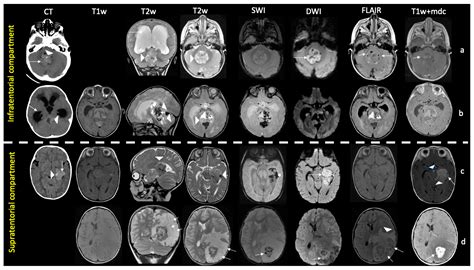

Diagnosis typically begins with advanced neuroimaging, such as MRI scans with and without contrast, to visualize the tumor's size and location. However, imaging alone is rarely sufficient. A definitive diagnosis is achieved through a surgical biopsy or total resection, followed by a rigorous pathological examination. Pathologists look for the loss of INI1 protein expression in the tumor cells, which serves as a molecular hallmark for an Atypical Teratoid Tumor.

• Atypical Teratoid Rhabdoid Tumor MRI